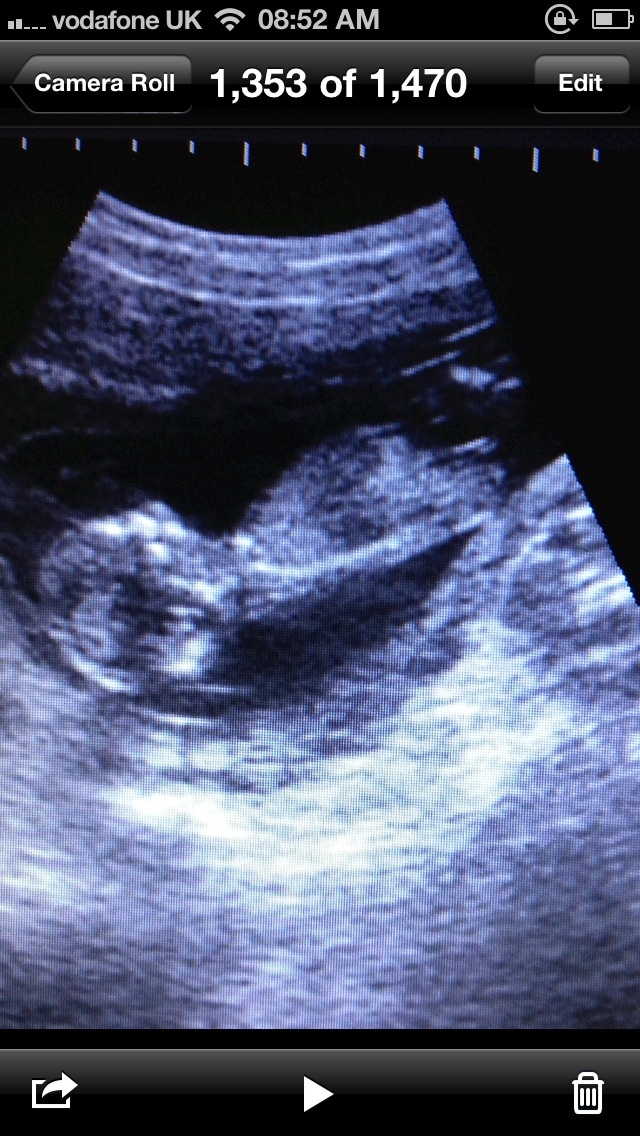

Can you please help me guess the gender of baby number six thank youAttachment 13674Attachment 13675Attachment 13676Attachment 13677